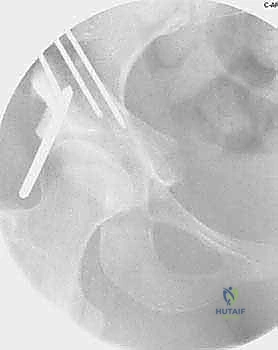

Operating Room Setup and Patient Positioning

Optimal patient positioning and operating room setup are critical for executing the complex geometry of the PAO safely. The patient is placed strictly supine on a fully radiolucent operating table. This is non-negotiable, as it allows for completely unrestricted, orthogonal fluoroscopic access throughout the entirety of the procedure. We utilize a C-arm fluoroscopy unit, positioned on the contralateral side of the operative hip, capable of swiftly providing AP, ilio-oblique, obturator-oblique, and false profile views.

Reorientation and Definitive Fixation

Once liberated, the acetabular fragment is highly mobile. Using the Schanz pin as a joystick, the acetabulum is reoriented to achieve the preoperatively templated coverage. Typically, this involves anterior and lateral rotation (extension and abduction of the fragment) and medialization of the hip center. The fragment is temporarily held with long Kirschner wires.

Intraoperative fluoroscopy is absolutely critical at this juncture. AP, false profile, and ilio-oblique views are obtained to confirm the correction of the LCEA, normalization of the Tönnis angle, and restoration of anterior coverage without inducing iatrogenic retroversion or femoroacetabular